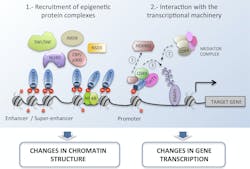

The initiation and progression of HNSCC and other cancers occur due to both genetic changes, such as genome instability and mutation, and dysregulation of the epigenome.7,8 Reversible epigenetic modifications —including DNA methylation, histone modification, chromatin remodeling and noncoding RNAs — regulate various cellular responses, and disruptions to these processes can lead to heightened expression of oncogenes, playing an important role in tumorigenesis. A classic example of this is the acetylation of lysine residues, a process mediated by histone acetyltransferases (HATs), at enhancer regions of oncogenes, such as c-MYC, BCL2 and CDK6. Histone acetylation can be recognized by proteins carrying bromodomains (BRDs) and, in turn, these epigenetic readers can recruit chromatin complexes to modulate transcription and activate the expression of oncogenes – such as E6 and E7 – that play an important role in cancer initiation and progression (Figure 2).9,10